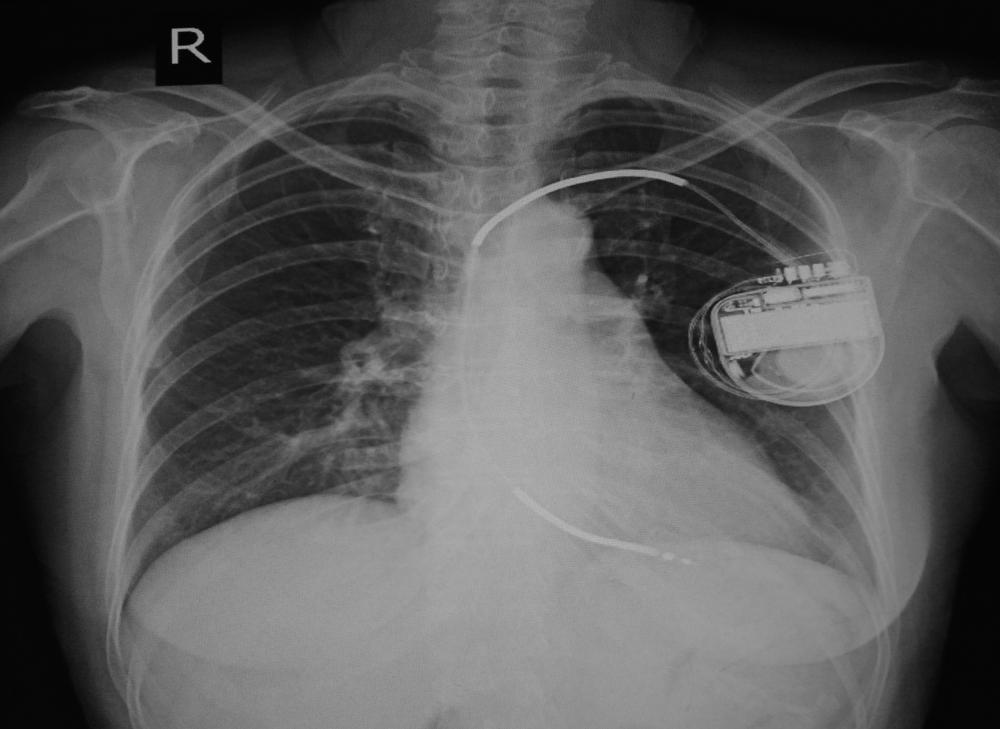

Menurut Robert Hauser, MD, seorang ahli jantung dari Minneapolis Heart Institute, Amerika Serikat, kedua kondisi tersebut dapat meningkatkan risiko kematian jantung mendadak dan gagal jantung. Oleh karena itulah dibutuhkan bantuan alat pacu jantung implan untuk membantu meningkatkan aliran darah ke jantung dan seluruh tubuh.

Sebelum memasang defibrilator, pastikan Anda sudah mengantongi izin dari dokter spesialis jantung Anda terlebih dahulu. Dokter akan melihat riwayat kesehatan Anda dan mengukur seberapa besar Anda membutuhkan pacu jantung.